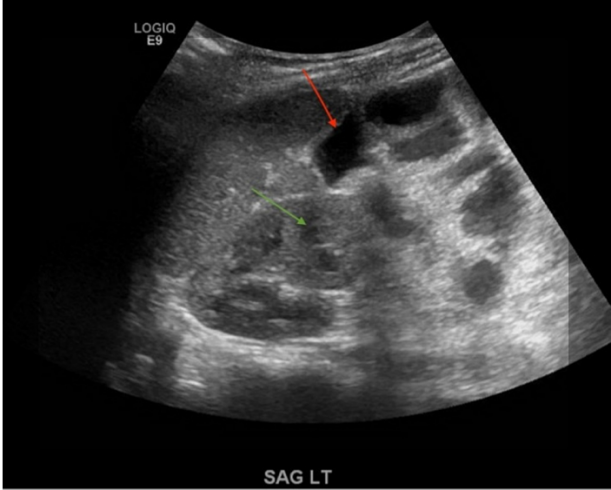

腹部超声检查无法定位任何病变,包括肾盂肾炎(图1)。腹部和骨盆的CT显示大量腹水,腹膜向腹盆交界处呈斑片状强化。大肠内可见低密度液体;升结肠扩张伴肠积气,可能存在肠缺血。在腹盆交界处发现一个长方形边缘强化集合。还有中等量的右侧肾周积液(图2)。

图1. 腹部超声检查显示右肾积水(绿色箭头)和肠袢突出(红色箭头)